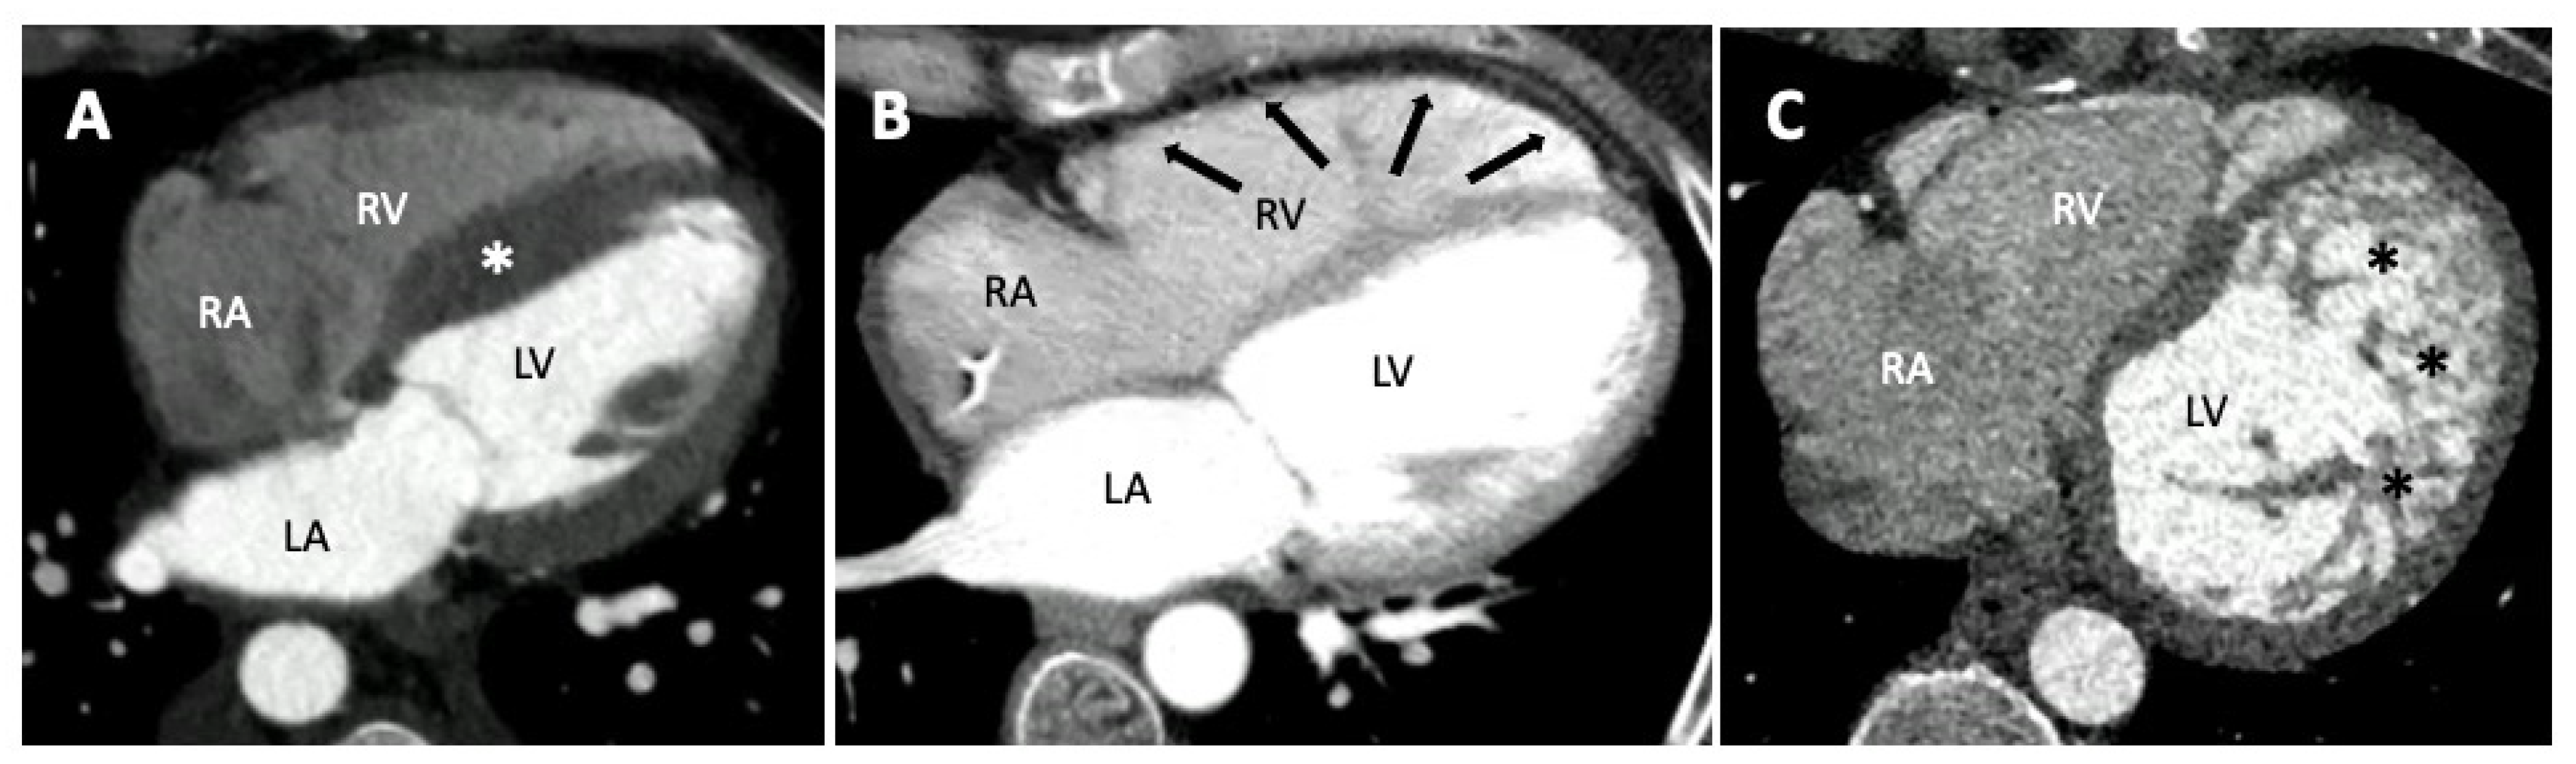

4.2. Role of CT in Paediatric Cardiomyopathies

4. Computed Tomography in Pediatric Cardiomyopathies

4.1. Protocols